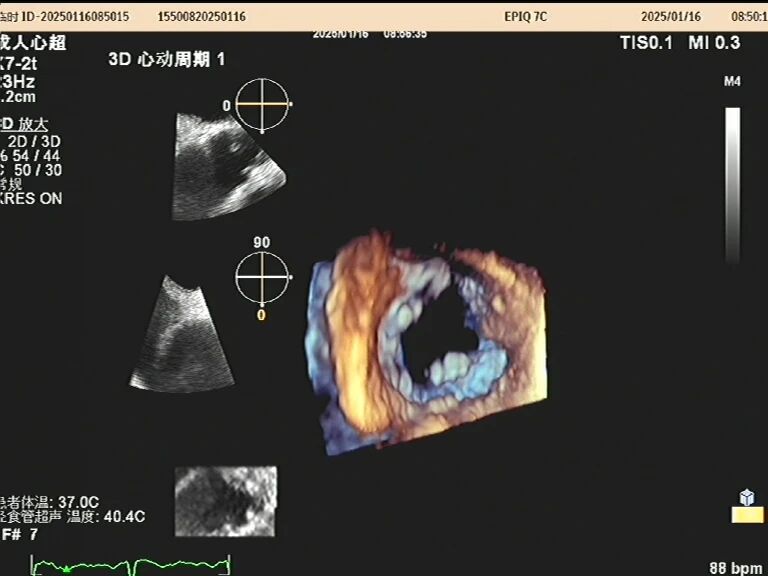

于是,一根如面条般柔软、顶端带着微型摄像头的探头,会从您的口腔缓缓进入食道。这个位置堪称完美,探头能紧贴着心脏,利用超声波为其拍摄一场无死角、超高清的“内部直播”。以前藏在背后的细微结构比如心耳里是否藏有血栓、人工瓣膜是否严丝合缝、心脏瓣膜上的小赘生物,此刻都一览无余。